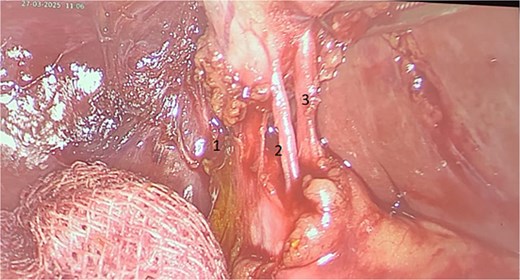

Surgery was performed after stabilization for elective cholecystectomy (Fig. 1). Intraoperatively, a double cystic duct was identified and managed successfully (Fig. 3). Pathology confirmed chronic cholecystitis with no malignancy.

Cholecystectomy specimen showing the three elements: Cystic artery (3) and two cystic ducts (1, 2).

Intraoperative image showing three elements: Cystic artery (3) and two cystic ducts (1, 2).